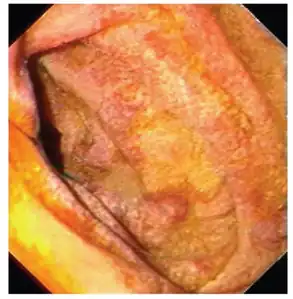

Endoscopy of the duodenum and jejunum can reveal pale yellow shaggy mucosa with erythematous eroded patches in patients with classic intestinal Whipple's disease, and small bowel X-rays may show some thickened folds. Other pathological findings may include enlarged mesenteric lymph nodes, hypercellularity of lamina propria with "foamy macrophages", and a concurrent decreased number of lymphocytes and plasma cells, per high power field view of the biopsy.

Mucosa is swollen and grey-yellowish